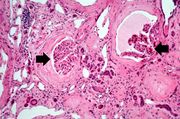

| 17:52, 19 August 2013 | IPLab5PolycysticKidney7.jpg (file) | 66 KB | This high-power photomicrograph shows abnormal glomeruli (arrows) and some tubules. | 1 | |